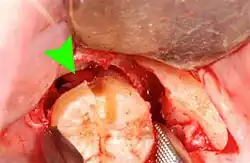

Wisdom teeth removal

Wisdom teeth removal (extraction) is the most common treatment for impacted wisdom teeth. In the US, 10 million wisdom teeth are removed annually.[21] The procedure can be either simple or surgical, depending on the depth of the impaction and angle of the tooth. Surgical removal is to create an incision in the mucosa of the mouth, remove bone of the mandible or maxilla adjacent the tooth, extract it or possibly section the tooth and extract it in pieces. This can be completed under local anaesthetic, sedation or general anaesthetic.[5] As of 2020, the evidence is insufficient to recommend one type of surgical practice over another.[22]

Coronectomy

Coronectomy is a procedure where the crown of the impacted wisdom tooth is removed, but the roots are intentionally left in place. It is indicated when there is no disease of the dental pulp or infection around the crown of the tooth, and there is a high risk of inferior alveolar nerve injury.[32]